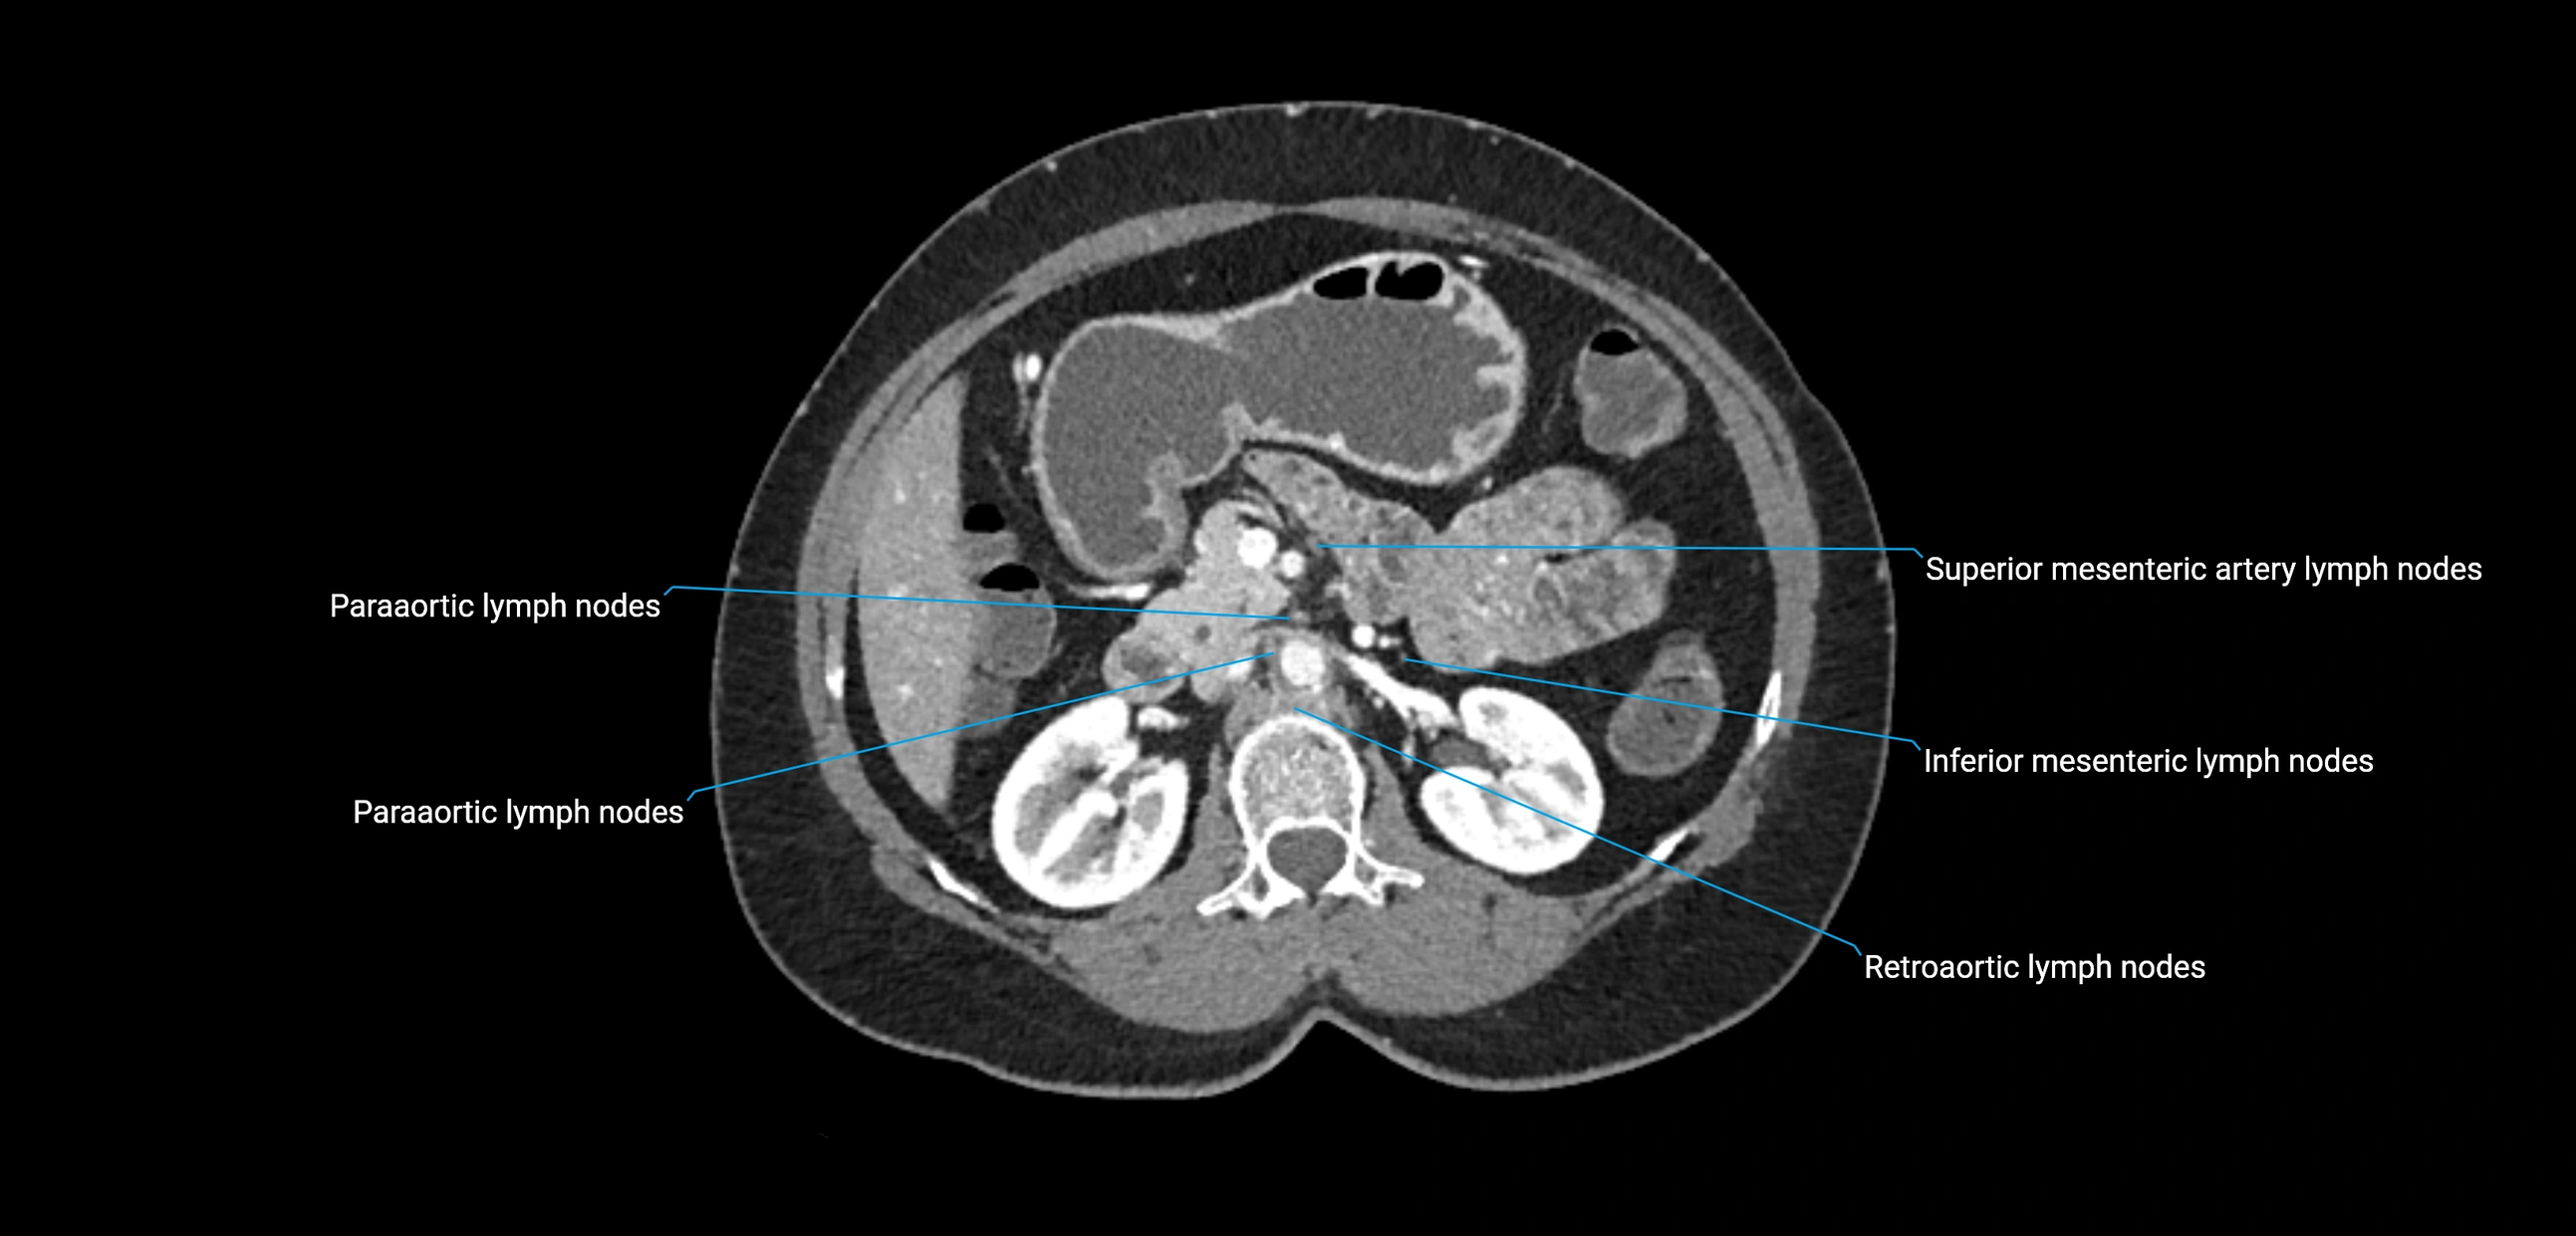

CT Appearance

CT Pre-Contrast:

• Nodes appear as soft-tissue density nodules adjacent to the aorta and IVC

• Calcification may be seen in chronic infections (e.g., tuberculosis)

CT Post-Contrast:

• Normal nodes enhance homogeneously

• Malignant nodes may show heterogeneous enhancement, central necrosis, or conglomerate formation

• Size >1 cm short axis is suspicious, though morphology and distribution are equally important

CT Venography (CTV):

• Demonstrates nodal encasement or compression of adjacent vessels (aorta, IVC, renal veins)

• Useful in staging testicular and ovarian malignancies

• Provides 3D reconstructions for retroperitoneal lymph node dissection planning

CT image

image